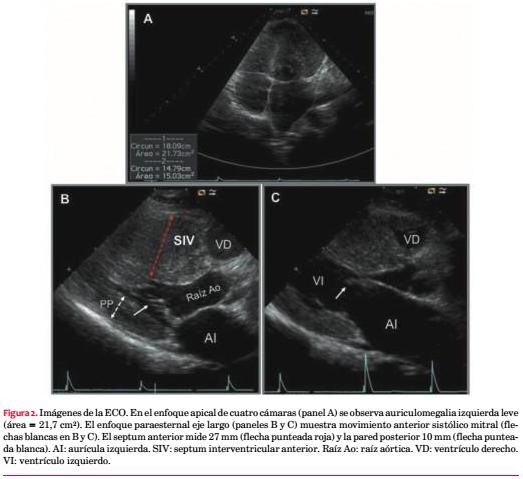

Paciente de sexo masculino, 21 años, sedentario, fumador intenso, exconsumidor de cocaína. No relata cifras elevadas de presión arterial (PA). Como antecedentes familiares destacaba la noción de padre, tío y hermano portadores de MCH, motivo por el cual concurre a control cardiológico ambulatorio. No presentaba antecedentes de MS en la familia. Mientras deambulaba presentó un episodio de pérdida brusca y transitoria de conocimiento, de escasos minutos, con recuperación ad integrum, precedido de dolor precordial. Hasta entonces el paciente manifestaba episodios ocasionales de palpitaciones rápidas, breves, en reposo. Examen clínico en la emergencia: paciente lúcido, eupneico, buen estado nutricional, con hematoma palpebral izquierdo. Al examen cardiovascular central no se palpaba el latido apexiano, ritmo regular de 60 cpm, S1 y S2 de tonalidad normal, soplo en mesocardio de intensidad II/VI (Levine) sin irradiaciones, que no se modificaba con la maniobra de Vasalva. Al examen vascular periférico, PA: 125/80 mmHg, pulsos simétricos normales, ausencia de ingurgitación yugular. Los campos pulmonares estaban libres y el examen neurológico era normal. El ECG basal de 12 derivaciones mostraba ritmo sinusal y marcadas alteraciones en la depolarización y repolarización ventricular (figura 1). La curva de biomarcadores de lesión miocárdica (TnI) fue negativa y el resto de la analítica de laboratorio fue normal.

Describimos el caso de un hombre joven con familiares portadores de MCH que consulta por síncope precedido de dolor torácico, situación clínica que sugiere la etiología cardiovascular del mismo. Sabiendo que en el 60% de los casos la MCH responde a una causa genética de transmisión autosómica dominante, más comúnmente a una o varias mutaciones en los genes que codifican proteínas sarcoméricas, planteamos que el paciente sea portador de una MCH. Los pacientes con MCH que presentan obstrucción al tracto de salida del VI suelen exhibir un soplo eyectivo en toda el área precordial que suele aumentar con la disminución en la precarga al VI inducida por las maniobras de Valsalva y cuclillas-bipedestación(2). En nuestro caso no se confirmó el comportamiento dinámico del soplo.